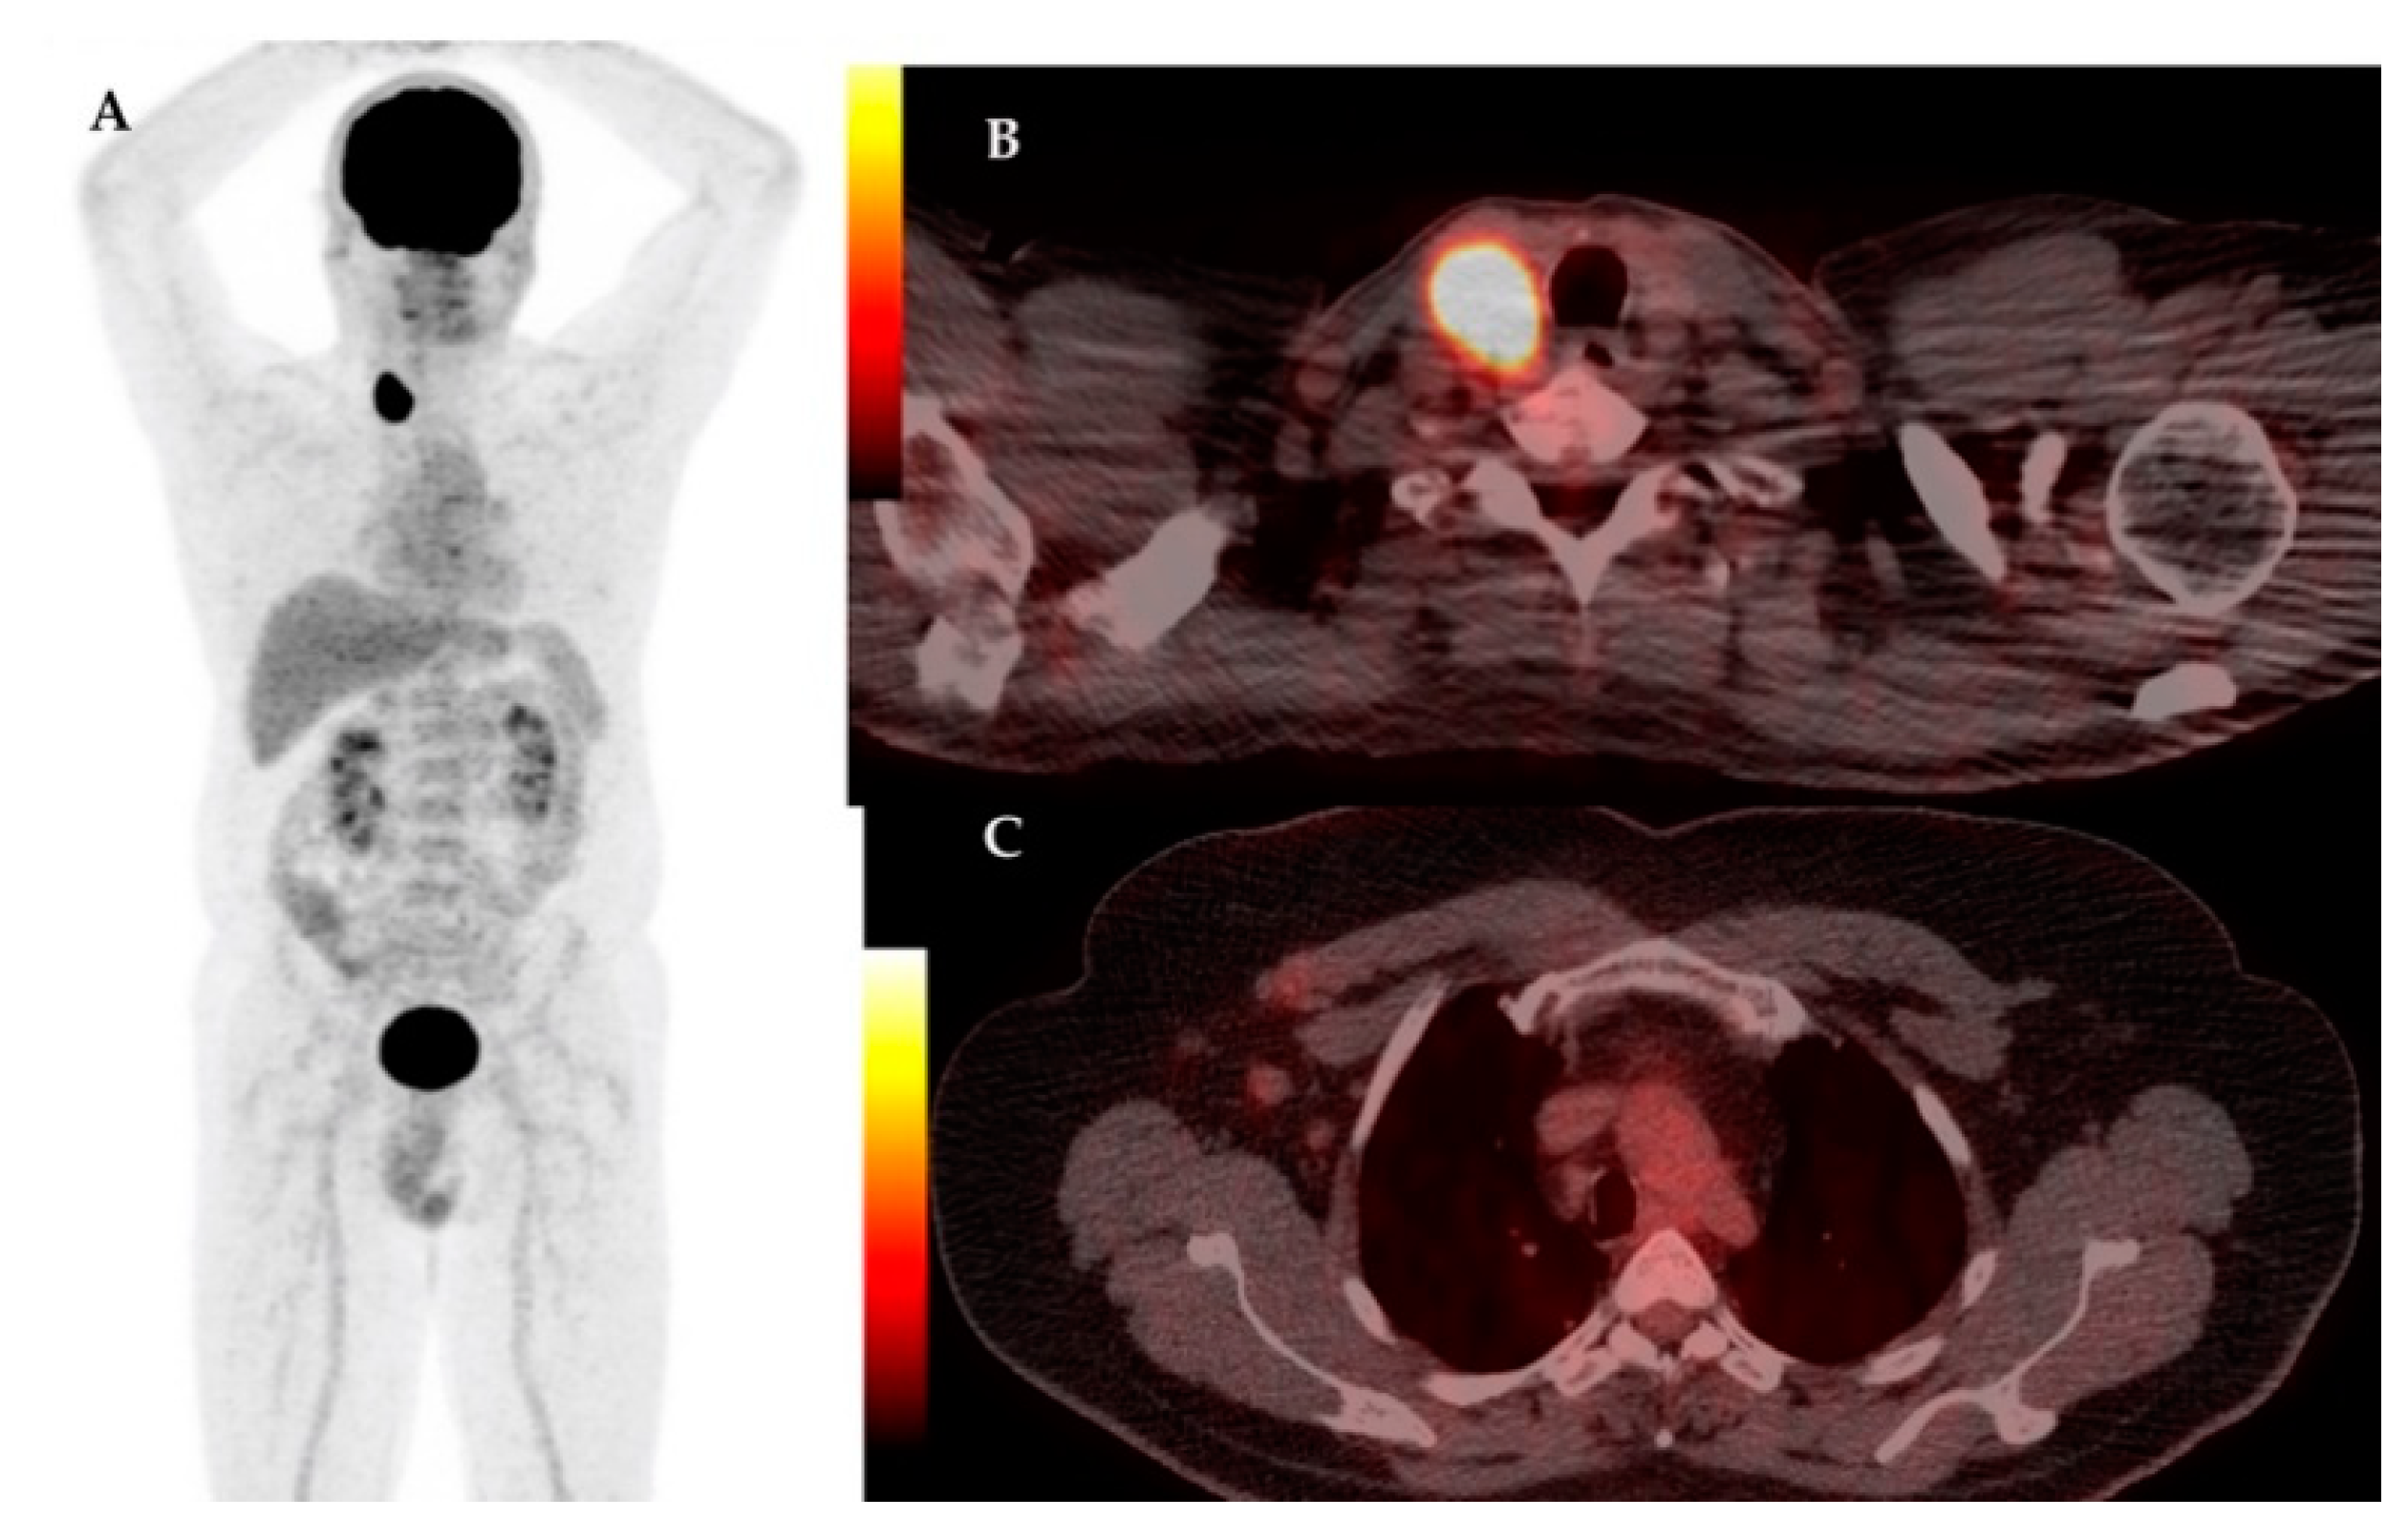

| 14 | 68 | IDC | RM + ALND | Yes | Yes | IIIB | LN | LN, Bn | 7.04 | Prostate cancer | 5.01– |